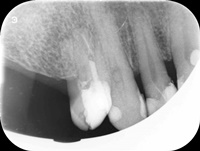

Przed trzema laty ząb 16 (prawa górna szóstka) był przeleczony endodontycznie i wykonano most. W ciągu 18 miesięcy od osadzenia mostu pacjentce kilka razy formował sie ropień dziąsła, osiem razy podawano antybiotyki. Gdy to nie pomagało, wykonano resekcję policzkowego korzenia zęba 16. Nie pomogło. W dalszym ciągu dochodziło do stanów zapalnych i antybiotykoterapii. W tym stanie pacjentka zgłosiła się, do naszego gabinetu. Zdjęto most, przeprowadzono ponowne leczenie kanałowe. Po sześciu miesiącach wykonano nowy most. Upłynęło półtora roku. Nie dochodzi do nawrotów stanu zapalnego, ani obrzęków. Ten przypadek pokazuje, dlaczego tak ważne jest poprawnie wykonane leczenie kanałowe, według nowoczesnego protokołu leczenia.